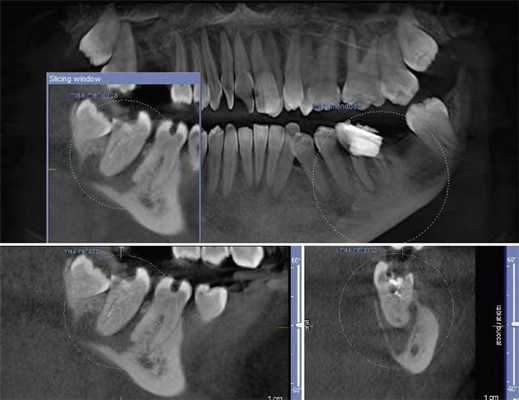

Ученые сообщили, что КЛКТ предоставляет более точные диагностические данные (61%) по сравнения с цифровыми (39%) и обычными (44%) рентгенограммами. Но, несмотря на то, что данные КЛКТ являются более точными, исследователи не призывают к полному вытеснению обычной внутриротовой рентгенографии для выявления периапикальных изменений в обычной клинической практике из-за финансовой и вредностной составляющих. Estrela и коллеги предложили использовать периапикальные индексы, основанные на КЛКТ, для идентификации патологий (Фото 4-6).

Фото 4: Периапикальная киста в переднем сегменте нижней челюсти

А: 3D изображение, показывающее большую кистозную полость

B: Изображение секционного распила, показывающее утрату кортикальной пластинки

C: Аксиальный вид, демонстрирующий утрату кортикальной пластинки с лабиальной стороны и интактную пластинку с лингвальной.

Фото 5: Хронические периапикальные абсцессы около первого правого нижнего моляра

Фото 6: Поражение периодонтальных тканей около левого верхнего второго моляра

Система индексов КЛКТ состоит из 6 ступеней (0-5), исходящих из определения самого большого размера повреждения в каком либо из измерений, и принятие в расчет расширение и разрушение кортикальной кости.

Применяя данный индекс, Low пришел к выводу, что в обнаружение периапикальных патологий лучше использовать КЛКТ недели обычную рентгенографию.